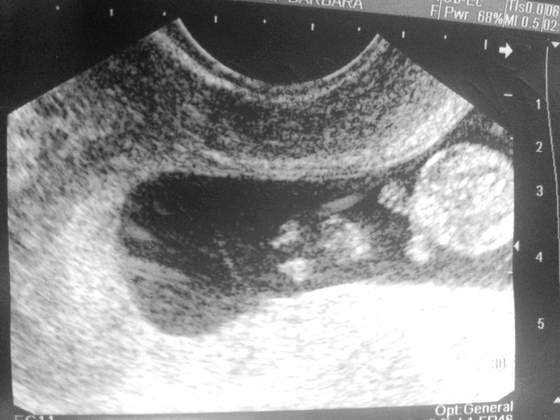

Boskie malenstwo!Tak jak obiecalam dziewczyny. Kolejne fotki mojej modelki/ modela ♡ Z dzisiaj tj. 9+2. Moja nowa milosc ma 27,05mm :-):-):-)

Zobacz załącznik 564201Zobacz załącznik 564200

ale sie usmialam z tego granata z zawleczkaEch, ile ja bym dała żeby mój jutro nie wyglądał jak granat z zawleczką... tylko jak człowieczek... Ale chyba za wcześnie by o tym marzyć. Może na kolejnym usg![]()